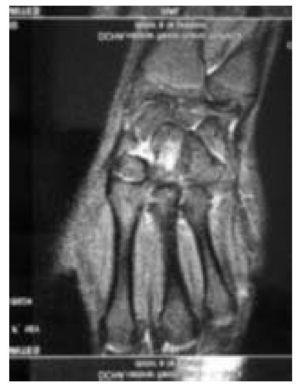

Degut a la llarga evolució de la lesió, es realitza ressonància magnètica (RM), que mostra una imatge suggestiva de fractura trabecular a nivell de l'os gran del carp dret amb escàs vessament i sinovitis de tendons extensors (fig. 2). Es complementa l'estudi amb escàner (TC), que mostra una fractura no desplaçada de cara volar de l'os gran en el seu terç mitjà sense desplaçament de fragment (fig. 3).

Figura 2 La imatge de RM mostra la fractura trabecular en l'os gran.